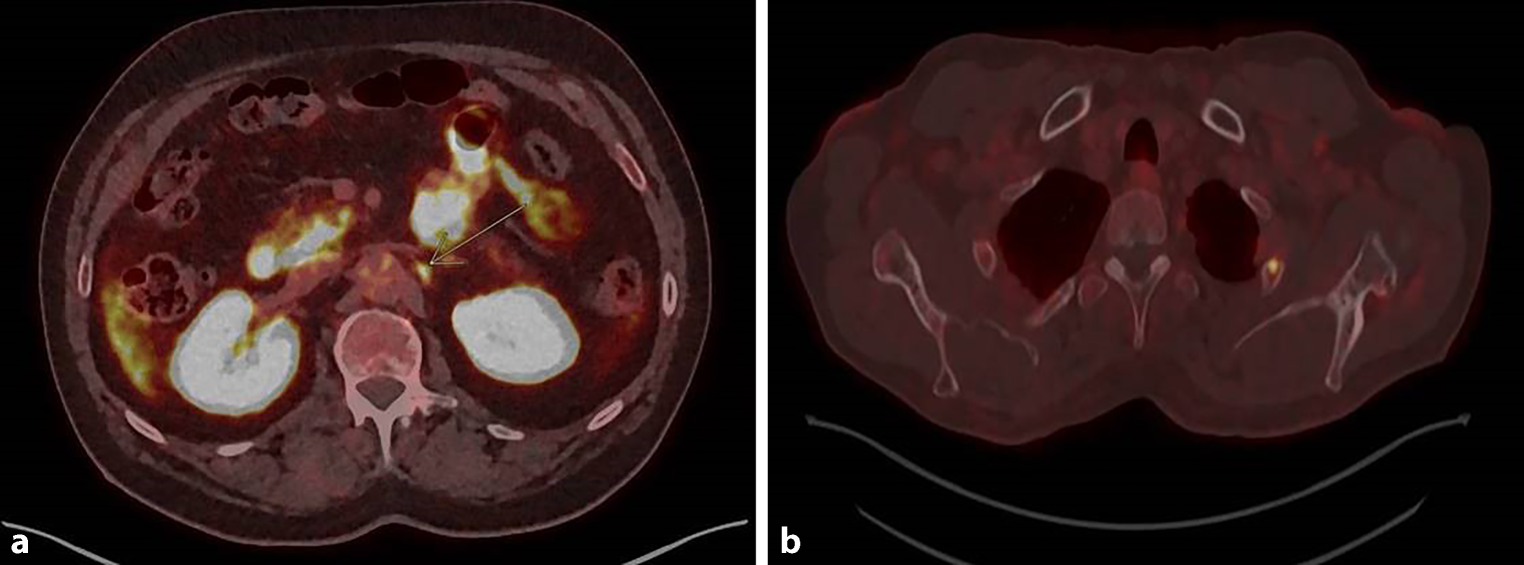

Het vastgestelde ziektevolume bij patiënten met mHSPC is sterk afhankelijk van de gebruikte beeldvormende techniek. De prostaatspecifieke membraanantigeen (PSMA)-PET/CT-scan heeft vergeleken met bot- en CT-scan een hogere sensitiviteit en specificiteit bij detectie van nodale laesies en metastasen op afstand [35]. Discriminatie tussen metastasen en aspecifieke afwijkingen (fig. 1) vraagt veel expertise van nucleair geneeskundigen. Het is denkbaar dat een patiënt een in opzet curatieve behandeling wordt onthouden als gevolg van een foutieve interpretatie van benigne laesies op PSMA-PET. Momenteel worden in de dagelijkse praktijk 68Ga- en ook 18F‑PSMA-PET/CT het meest gebruikt in de setting van een biochemisch recidief na in opzet curatieve therapie, conform de Nederlandse richtlijn [32]. Gezien het resultaat van de proPSMA-studie zou het vervangen van een botscan en CT-abdomen door PSMA-PET/CT een overweging kunnen zijn in de primaire diagnostiek van patiënten met hoogrisicoprostaatcarcinoom. De praktijk leert dat PSMA-PET/CT in toenemende mate wordt ingezet voor primaire stadiëring van patiënten met zowel intermediair- als hoogrisicoprostaatcarcinoom. Bij gebrek aan prospectieve studies die een overlevingsvoordeel aantoonden van primaire stadiëring met PSMA-PET moet men rekening houden met het nemen van therapeutische beslissingen op basis van uitkomsten van PSMA-PET, zodat patiënten geen curatieve behandeling onthouden wordt.

Figuur 1

Fout-positieve afwijking in een coeliacus ganglion (a) en een aspecifieke riblaesie (b) op een PSMA-PET-scan van een patiënt met prostaatcarcinoom